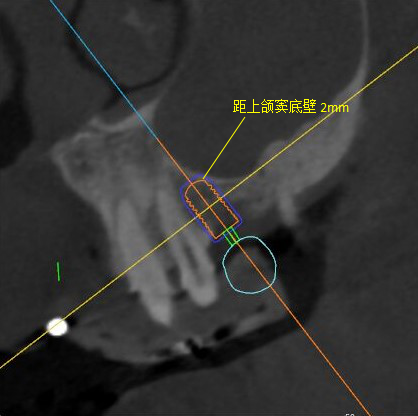

觀察患者CT,可看出患者有上頜竇粘膜囊腫,粘膜囊腫為竇內(nèi)腺體阻塞所致,視情況可有手術(shù)摘除和不予處理兩種方法,此次患者拒絕手術(shù)摘除,故需規(guī)避上頜竇位置。

冠狀面視圖

矢狀面視圖

軸狀面視圖

三維視圖

根據(jù)患者CT顯示,使用種植導(dǎo)航軟件設(shè)術(shù)前手術(shù)方案??紤]到患者拒絕手術(shù)摘除上頜竇囊腫等因素,此次手術(shù)選用了Straumann骨水平4.10*8.0mm的植體,植體末端位點(diǎn)設(shè)計(jì)距上頜竇底壁2mm處的同時(shí)兼顧種植方向和修復(fù)間隙,來(lái)達(dá)到理想的效果。